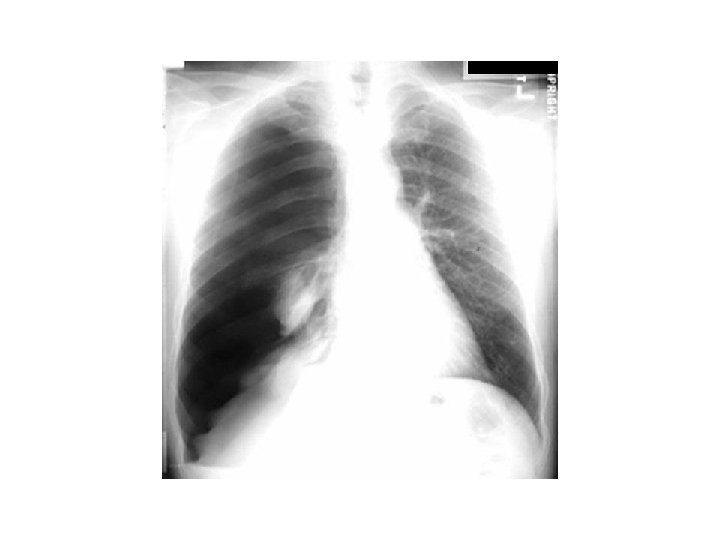

Cas clinique 2 • • • M O. , 55 ans, douleur thoracique droite, brutale, non fébrile tabagisme à 50 PA, sevré il y a 1 an diminution du murmure vésiculaire crépitement sous cutané

• Diagnostic ? • Traitement ?